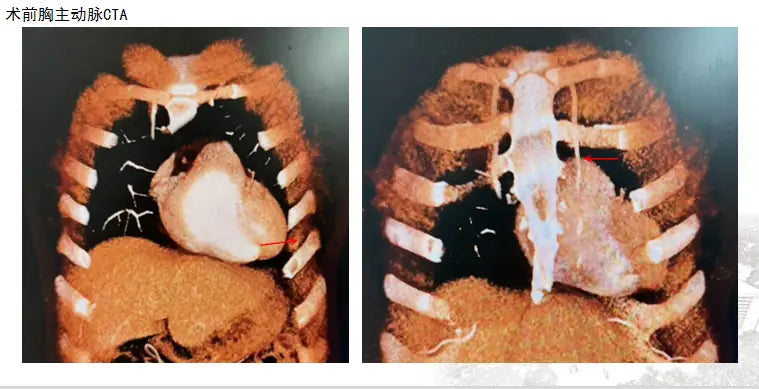

Upon admission, Dr. Xia Dongsheng and his team conducted a series of rapid tests. The results showed elevated high-sensitivity troponin T levels, suggesting a risk of myocardial damage. A combination of her medical history, including hypertension and prior vocal cord surgery, along with coronary angiography and chest CT, revealed significant coronary artery disease. The multidisciplinary team quickly convened to develop a treatment plan.

After careful consideration, the experts concluded that the patient was a suitable candidate for a minimally invasive coronary artery bypass grafting (CABG). This approach, which involved a small incision, would precisely reopen the blood supply to the heart while minimizing surgical trauma and accelerating recovery.